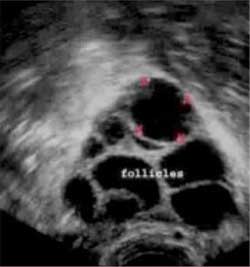

Menogon injection for ovulation. It is a hormonally active drug that stimulates the production of eggs in the ovaries in cases of women who suffer from ovarian failure. It is used to treat infertility in any of the following situations. This medication is extricated from the urine of postmenopausal females. Kinderwunschzentrum an der wien obruca strohmer 46 542 views 3 11.

In women who do not ovulate and do not respond to treatment with clomiphene citrate menogon 75iu can be used to cause ovulation. Although the commonly used fertility drug clomiphene is taken in pill form a great many of the drugs required for women being treated for infertility necessitate getting a shot typically many shots over a period of days to weeks. It is a hormonally active drug that stimulates the production of eggs in the ovaries in cases of women who suffer from ovarian failure. Menogon injection is used to treat infertility in women.